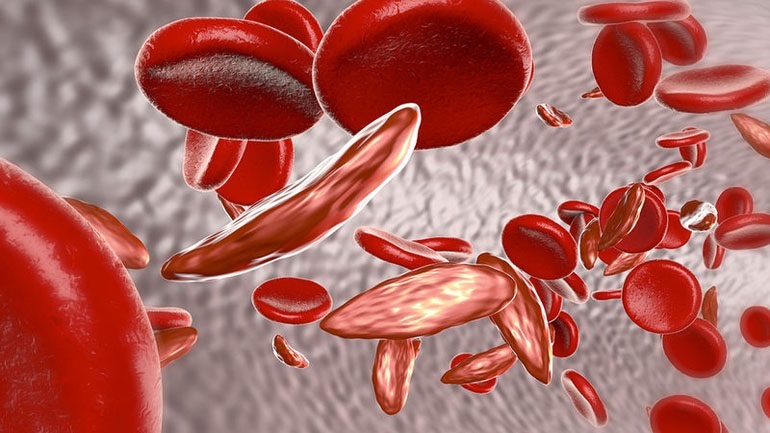

Κινήσου ενάντια στη θρόμβωση

Το μήνυμα «Κινήσου ενάντια στη θρόμβωση» ήταν το κεντρικό μήνυμα όλων των ομιλητών κατά τη διάρκεια Συνέντευξης Τύπου που οργάνωσε το Ι.Μ.Ε.Θ.Α., με αφορμή τον εορτασμό της Παγκόσμιας Ημέρας Θρόμβωσης (13 Οκτωβρίου). Ο εορτασμός της Παγκόσμιας Ημέρας Θρόμβωσης που φέτος κλείνει τα 10 χρόνια, έχει την επιστημονική αρωγή 19 Επιστημονικών Εταιρειών που σχετίζονται με τη […]